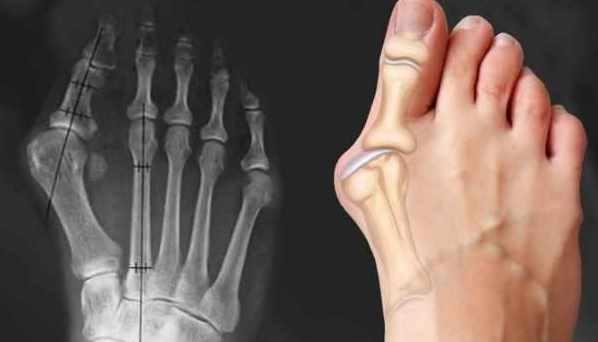

Новый онлайн-курс по массажу при проблемах связанных с искривлением большого пальца стопы, образованием "шишки", "косточки" на ноге, плоскостопии и сопутствующих патологиях

Урок №4. Система большого пальца стопы. Вальгусная деформация, механизм развития патологии, биомеханика

Урок №5. Методика и техника массажа при вальгусной деформации большого пальца стопы. Протокол работы